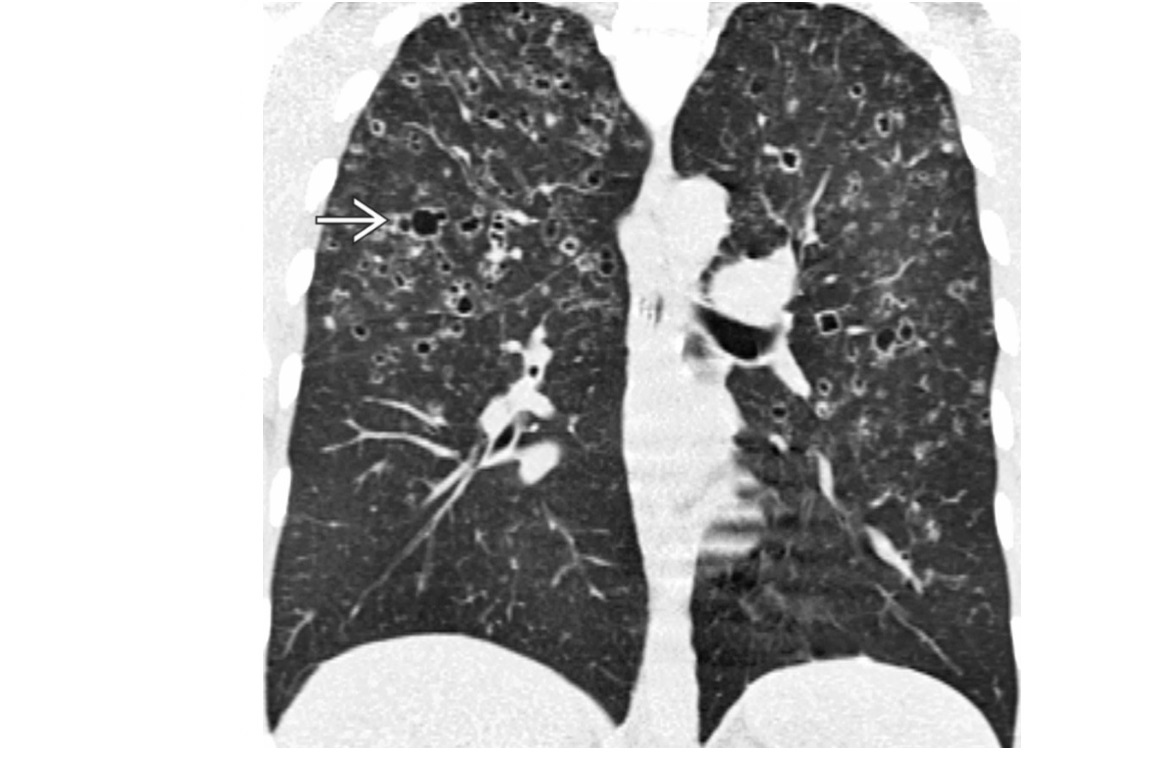

MAC

Tree in bud - terminal bronchiole filled with radiopaque material

cylindric bronchiectasis

clasically right middle lobe or lingula (aka lady windermere syndrome)